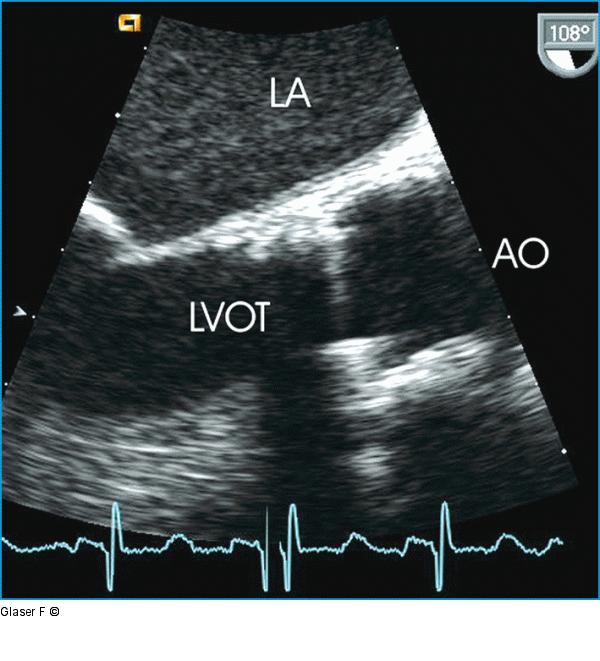

Abbildung 7: Transösophageales Echo - Aortenklappe Transösophageales Echo der Aortenklappenprothese (Längsachse, 108°): Das Klappenspiel ist nicht ausreichend beurteilbar, beachte aber die enge A. ascendens im Anschluß an die Prothese (deutlich kleiner als 3 cm). |

Transösophageales Echo der Aortenklappenprothese (Längsachse, 108°): Das Klappenspiel ist nicht ausreichend beurteilbar, beachte aber die enge A. ascendens im Anschluß an die Prothese (deutlich kleiner als 3 cm). |